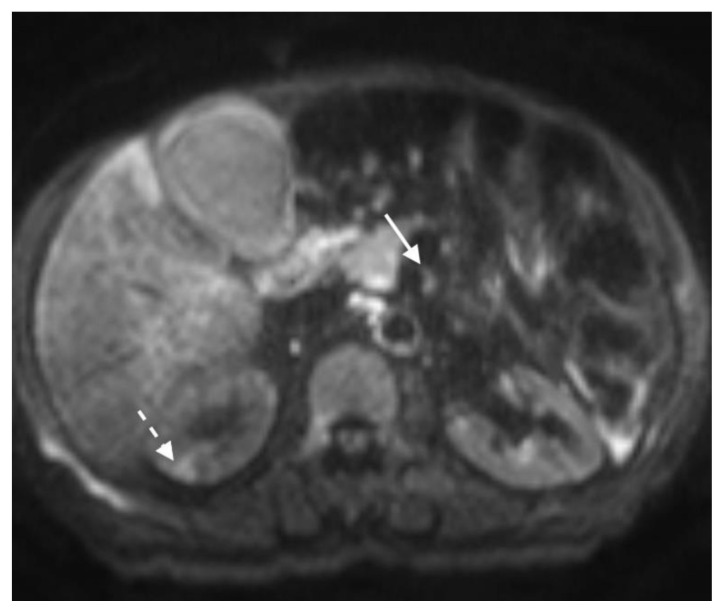

Figure 9.

78 year-old male with IgG4-related autoimmune disease.

Findings: Contrast enhanced MRI demonstrates enhancing soft tissue around the SMA (solid arrow). Also note lack of hypoenhancement in the renal kidneys (dashed arrow).

Technique: Axial T1-weighted fat saturation (6.7 mL Gadavist). 1.5T, TR = 5.86, TE = 0, 2.5 mm slice thickness.

The MRI revealed soft tissue encased the proximal common bile duct (CBD) and biliary hilum, resulting in a 4cm-long stricture, with increased upstream intrahepatic biliary dilatation (Figures 5, 6). The hepatic parenchyma demonstrated diffuse heterogeneous enhancement, without a focal mass or pseudotumor, consistent with inflammatory changes. The pancreas demonstrated parenchymal T2 hyperintensity and T1 hypointensity with diffuse enhancement, including an enhancing peripheral soft tissue rind, again consistent with autoimmune pancreatitis (Figure 7). The kidneys also demonstrated multifocal regions of abnormal enhancement and restricted diffusion (Figure 9, 10). Persistent enhancing soft tissue surrounding the SMA and IMA was again noted (Figure 11, 12).